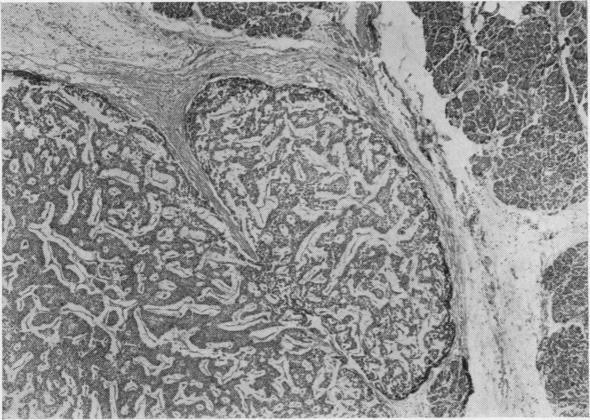

The association of bronchial carcinoid and pluriglandular adenomatosis.

Thorax. 1962 Jun;17(2):120-7. doi: 10.1136/thx.17.2.120.